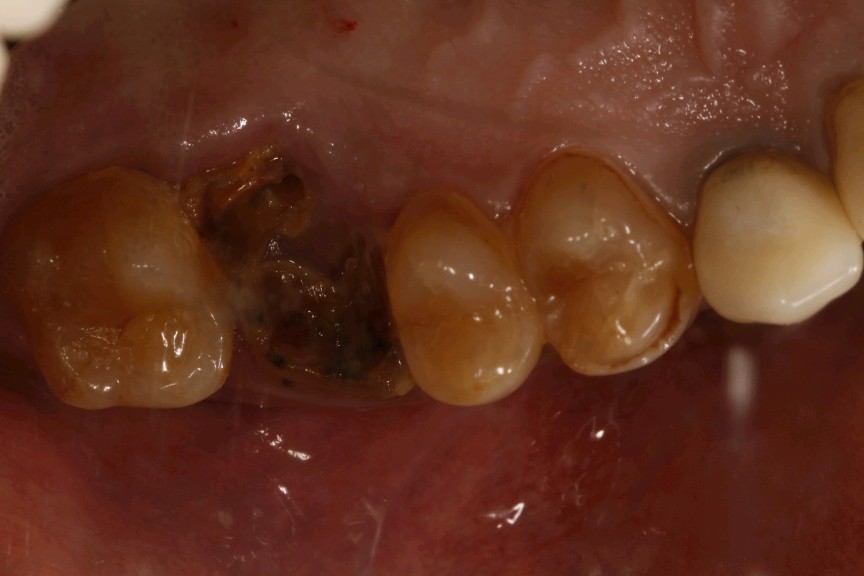

患者男,52 岁。 多年前曾在外院做过根管治疗及桩核冠修复,近一年来桩核冠常有脱落,反复粘接史,三日前桩冠脱落后丢失,前来我院就诊。

口腔检查图片

治疗方案:拔出后种植修复。